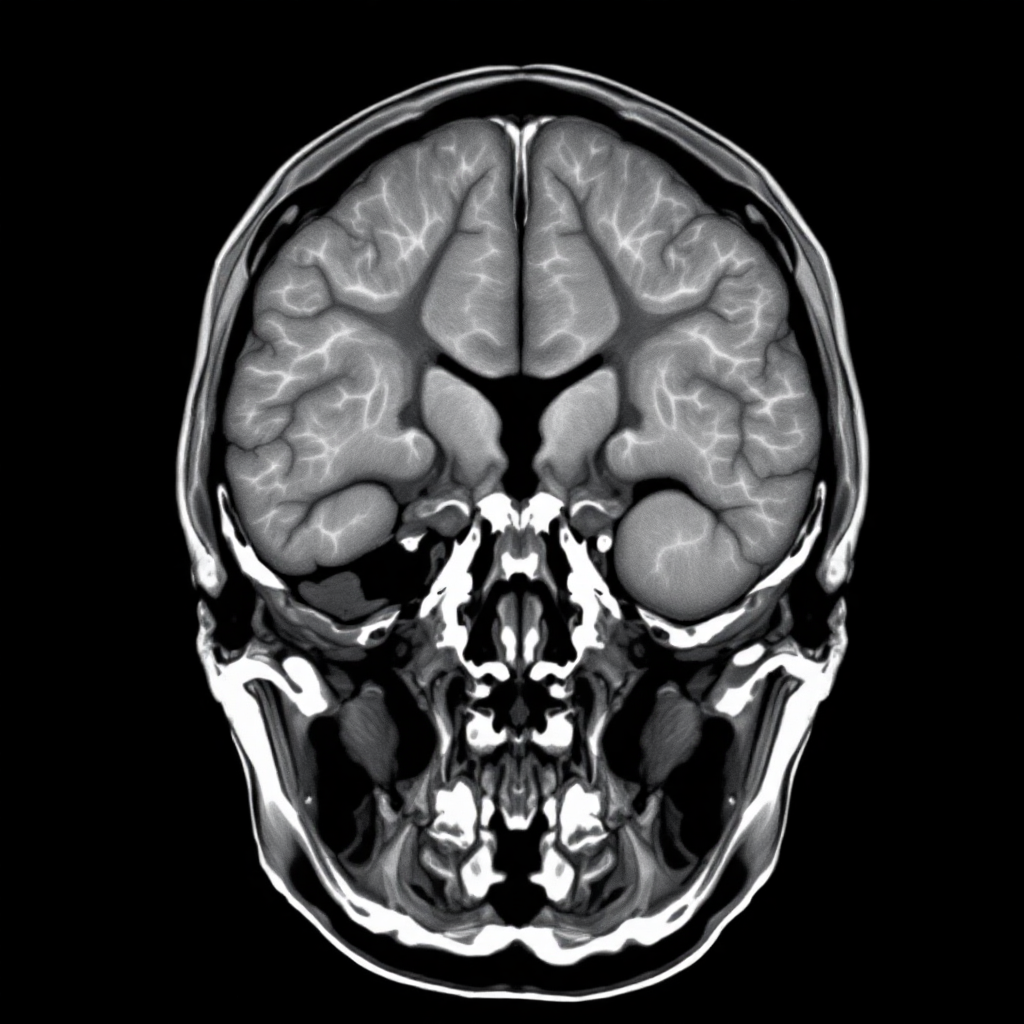

뇌 CT 검사의 핵심은 뇌 조직의 밀도 차이를 영상으로 보여주는 것이에요. 뼈는 하얗게, 뇌조직은 회색으로, 뇌척수액이나 출혈은 각각 다른 농도로 나타나기 때문에 의사들이 이를 통해 뇌의 이상 유무를 판단할 수 있어요. 특히 급성 뇌출혈의 경우 CT에서 매우 밝게 보이기 때문에 응급상황에서 빠른 진단이 가능하답니다.

뇌 CT 결과를 해석하는 것은 전문의의 영역이지만, 기본적인 원리를 이해하면 검사 결과를 받았을 때 도움이 되요. CT 영상에서는 조직의 밀도에 따라 다른 색깔로 나타나요. 뼈와 같이 밀도가 높은 부위는 하얗게(고밀도), 뇌조직은 회색으로(중등도 밀도), 뇌척수액이나 공기는 검게(저밀도) 보여요. 이런 밀도 차이를 통해 정상과 비정상을 구분할 수 있답니다.

뇌출혈은 CT에서 가장 쉽게 발견할 수 있는 이상 소견이에요. 급성 뇌출혈은 주변 뇌조직보다 밝게 나타나기 때문에 한눈에 봐도 확인이 가능해요. 출혈의 위치에 따라 뇌내출혈, 지주막하출혈, 경막하출혈, 경막외출혈 등으로 분류되고, 각각의 치료법과 예후가 다르답니다. 출혈의 크기와 위치는 환자의 증상과 치료 방침을 결정하는 중요한 요소가 되어요.

뇌경색의 경우 CT에서는 초기에는 잘 보이지 않을 수 있어요. 뇌경색은 뇌조직으로의 혈액 공급이 차단되어 뇌세포가 죽어가는 과정인데, 이 변화가 CT에서 확인되려면 보통 6-12시간 정도 걸려요. 초기 뇌경색은 정상 뇌조직보다 약간 어둡게 보이거나 뇌부종으로 인한 변화로 나타날 수 있어요. 시간이 지나면서 뇌경색 부위는 더욱 어둡게 변하고 뚜렷해져요.

뇌종양은 CT에서 다양한 모습으로 나타날 수 있어요. 종양의 종류, 크기, 위치에 따라 다르게 보이는데, 대부분 정상 뇌조직과 다른 밀도를 가져요. 조영제를 사용하면 종양으로의 혈류 공급 상태를 확인할 수 있어서 양성 종양과 악성 종양을 구별하는 데 도움이 돼요. 종양 주변의 뇌부종도 함께 관찰할 수 있어서 종양의 악성도를 추정하는 데 중요한 정보가 됩니다.